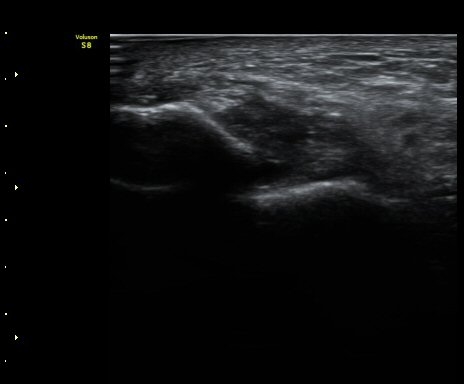

Àü°Å°ñºñ°ñÀδë Á¾´Ü¸é°Ë»ç¿¡¼­ ÀδëÀÇ Àú¿¡ÄÚ ºÎÁ¾ÀÌ °üÂûµÈ´Ù(±×¸² 2).